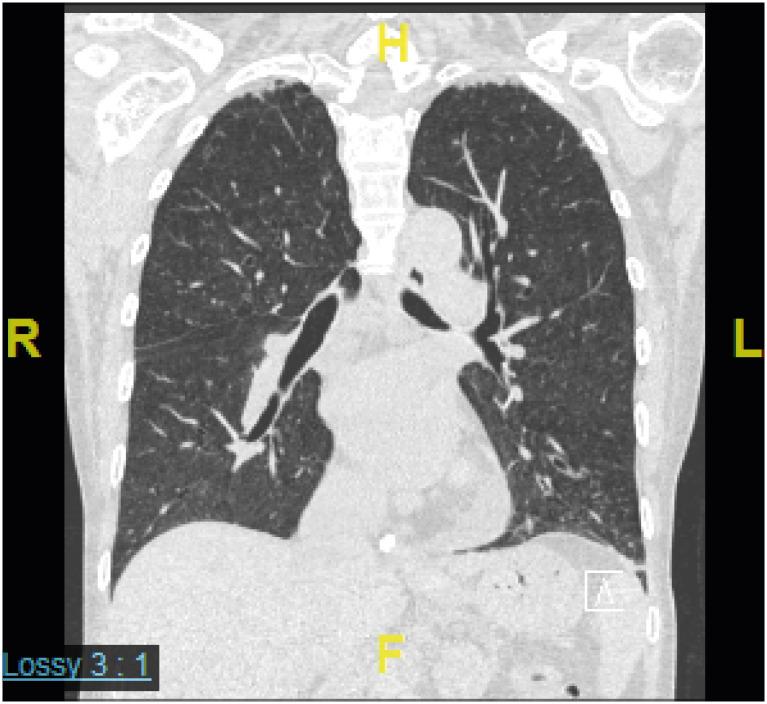

古德综合征(GS)是一种原发性免疫缺陷病(PID),多见于中老年人,伴有胸腺瘤、低丙种球蛋白血症、CD4 T淋巴细胞减少、CD4/CD8 +比值倒置以及T细胞丝裂原增殖反应受损等特征。我们报告一例62岁女性患者,最初表现为乙型肝炎病毒(HBV)再激活导致的急性肝炎,随后因反复肺炎和巨细胞病毒性肠炎反复发作而多次住院。后来发现她患有胸腺瘤和低丙种球蛋白血症,被诊断为GS。虽然T细胞在胸腺瘤免疫病理学中指导B细胞反应的重要性已广为人知,但自然杀伤细胞和CD4 +γδT细胞水平较低也可能是肿瘤发生的免疫监视低下和病毒感染清除能力减弱的原因。因此,HBV再激活后机会性感染与发现胸腺瘤的时间顺序可能反映了作为PID首发表现的免疫监视丧失。